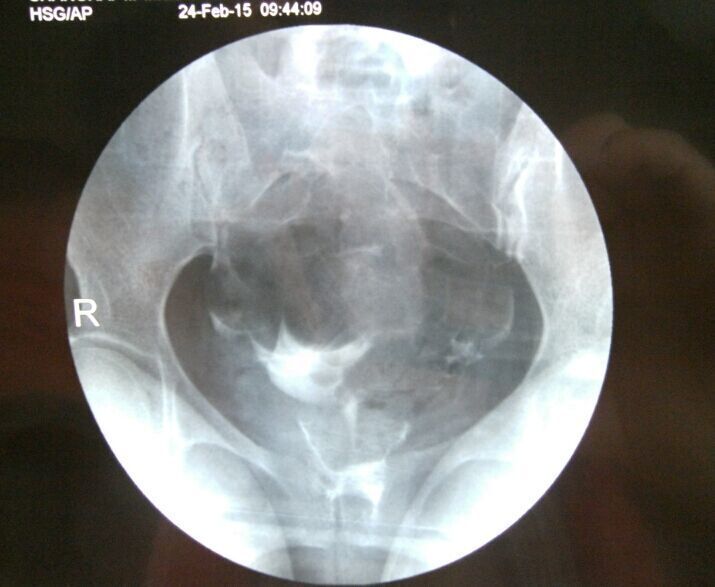

双侧输卵管通而不畅选择哪种治疗方案,谢谢 1、结婚1年多没有做避孕措施;2、我88年,我老公87年,老公检查没什么问题;我做常规检查都正常,在当地三甲医院做过B超(见上传图片),做过6项雌激素(见上传照片);3、量基础体温有排卵,但是拿大卫测试纸却不显示排卵。做过一段时间中药还是没怀孕,现在不知道下一步怎么办?求得解决,谢谢…… 造影报告写着:放射学表现:盆腔平片:盆腔内未见异常密度影。注入造影剂后即刻盆腔摄片:宫腔大小形态正常,腔壁光整。双侧输卵管显影,形态柔软。20分钟后复查摄片:盆腔内见造影剂均匀涂抹,双侧输卵管内少量造影剂残留。放射学诊断:子宫腔正常,双侧输卵管通而不畅。 点击展开 匿名用户 2015-03-06 21:29 为您推荐: 其他回答 你好,联系下次月经过后3-7天内可以去做个输卵管通液,一般是有效果的 天使7737 2015-03-06 23:07 相关问题 您好,我现在双侧输卵管通而不畅,我想治疗,有什么方法吗? 双侧输卵管通而不畅有哪些治疗方案 有没有懂中医的人,帮我看看这个方子和这个治疗方案,谢谢 我是通过造影查出双侧输卵管通而不畅

1、结婚1年多没有做避孕措施;2、我88年,我老公87年,老公检查没什么问题;我做常规检查都正常,在当地三甲医院做过B超(见上传图片),做过6项雌激素(见上传照片);3、量基础体温有排卵,但是拿大卫测试纸却不显示排卵。做过一段时间中药还是没怀孕,现在不知道下一步怎么办?求得解决,谢谢…… 造影报告写着:放射学表现:盆腔平片:盆腔内未见异常密度影。注入造影剂后即刻盆腔摄片:宫腔大小形态正常,腔壁光整。双侧输卵管显影,形态柔软。20分钟后复查摄片:盆腔内见造影剂均匀涂抹,双侧输卵管内少量造影剂残留。放射学诊断:子宫腔正常,双侧输卵管通而不畅。